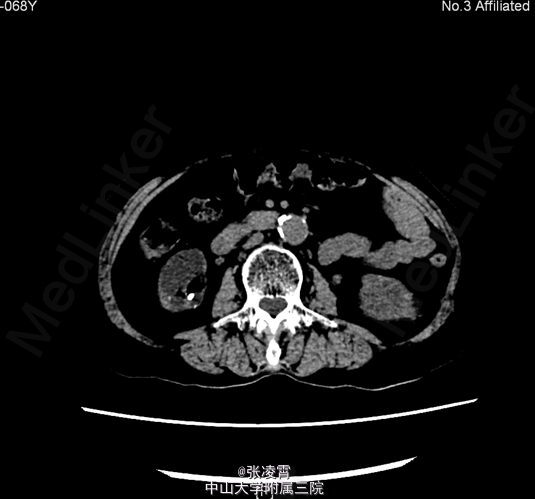

患者,女性,68岁,因“双侧腰部疼痛1周“入院。患者1周前无明显诱因下出现双侧腰部隐痛,可忍受,每次持续1小时,有尿频、尿急、间接性尿痛,有夜尿,每夜可达4次。 既往史:2010年及2012年于我院泌尿外科二区行经皮肾镜碎石术

当地医院B超提示:肾功能受损改变,右肾多发结石。 CTU:1、双肾多发结石,双肾轻~中度积液、炎症;双肾萎缩,双肾功能减低2、双肾多发囊肿3、腹主动脉、双侧髂动脉硬化 核素肾动静态显像:1、右肾灌注、功能中度受损,右上尿路不完全性梗阻可能性大。2、左肾灌注、功能中度受损。 肌酐:281.000umol/L 尿素氮:14.220mmol/L 尿常规:白细胞计数 28.1个/ul

诊断:1.双肾结石 ;2.泌尿道感染;3.肾功能不全 经完善相关术前检查,予行双侧输尿管软镜下碎石术。手术耗时约3小时,手术顺利,出血约5ml。

此患者双侧肾功能都不是很好,入院前有双侧腰腹部疼痛的情况,并且有尿路感染,考虑还是结石导致的感染。患者进行ECT检测发现左侧GFR为23.93,右侧为14.69。一般来说GFR小于10可以考虑直接行肾切手术。该患者还没有做肾切的指征,并且双侧肾结石都不大,行经皮肾镜对肾脏损害较大,综合考虑做输尿管软镜应为最佳手术方式。